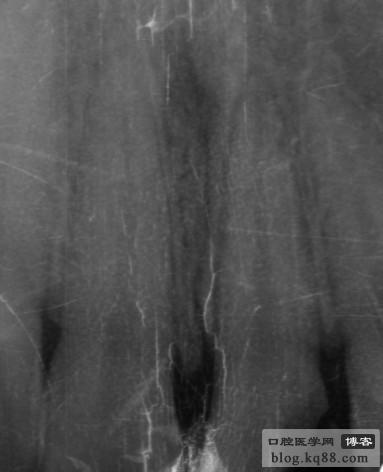

總有個(gè)夢(mèng)想,想把彎曲根管和側(cè)支根管都做到完美根充,但是夢(mèng)還在繼續(xù)。下面是我這段時(shí)間幾個(gè)病例:

千變?nèi)f化的根管猶如千千世界,需要我們?nèi)ンw驗(yàn)去感悟,完成心中的夢(mèng)想,就要從點(diǎn)滴做起,拍片、開髓、直線通路、根上部預(yù)備、疏通根管、沖洗、大錐度預(yù)備、試尖、拍片、糊劑、熱壓、回填、拍片,仿佛每一步都不能小視,猶如上層建筑,需要一層一層搭建,才能達(dá)到夢(mèng)想的高度。